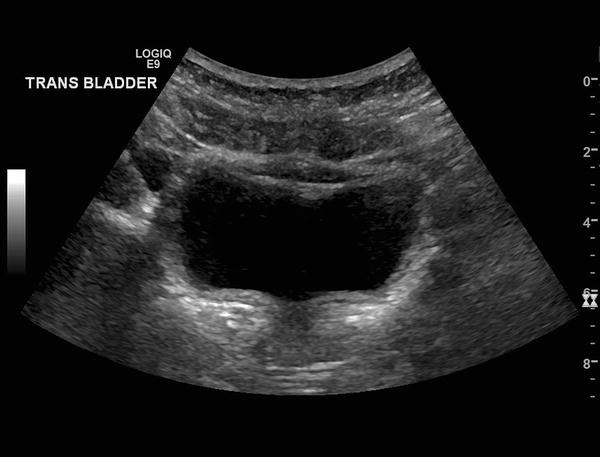

This image shows a bladder with thin walls no intraluminal lesions and slightly particulate urine content. Second image shows bladder ultrasound with echogenic debris and a stone appearing as hyperechoic curved structure with a shadow. The echogenic material could be a blood clot also.

Usually but not always debris moves with moving the patient while clot remains adherent to the bladder wall. Blood clots in the urinary bladder usually form echogenic masses without acoustic shadow and without visible blood flow in Doppler examination fig. They usually move when the patient changes position.